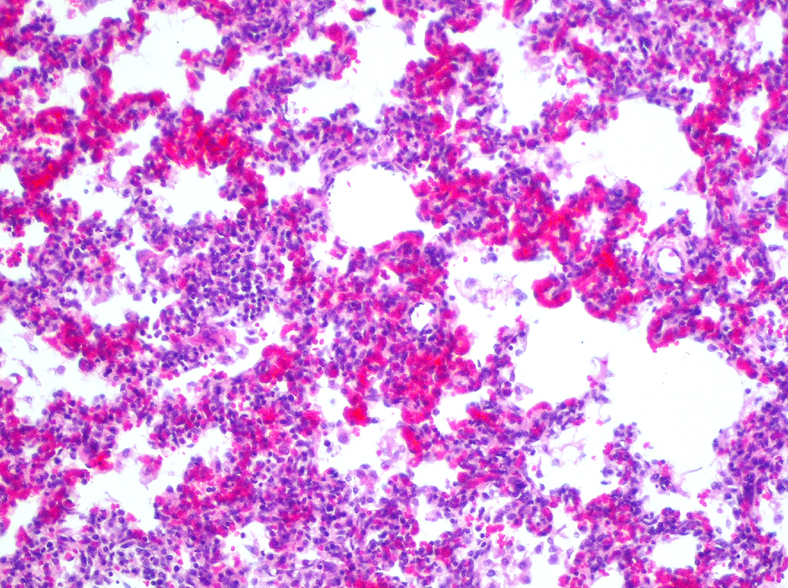

identify lesion:

What is its Morphology?

Interstitial pneumonia

Necrosis of type 1 epithelial cells and hyaline membrane formation

(Type 1 – most sensitive to damage and loss of integrity (intra-alveolar)

Morphology: